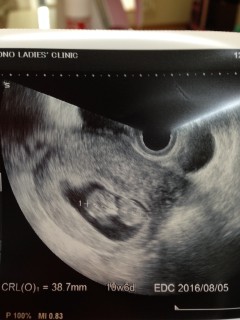

写真:10w4d:さくらさん

10w4d 大きさ42mm

2週前の検診時から、倍の大きさに。

今回は寝ているのか、じっと大人しいぼうや。心臓はトクットクッと元気に動いており、心音からも元気なのが伝わりました。先生からも順調とのお言葉をいただき安心ました。

今日のぼうやの見た目はまるで遠い星からやって来たグレイ!2週間後の検診が今からとても楽しみです。